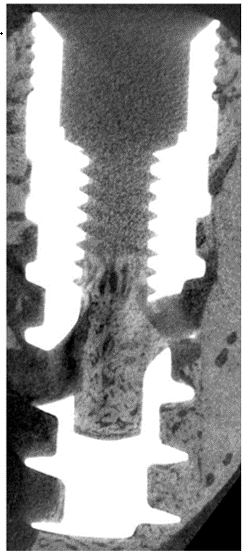

3-D Integration, Visualized

Micro-CT observations in preclinical models show bone ingrowth into the internal chamber, supporting multi-directional fixation research.

Micro-CT image showing bone ingrowth into internal chamber of KiiS

Micro-CT (10μ) in canine mandibular bone — 6 weeks post-implantation.